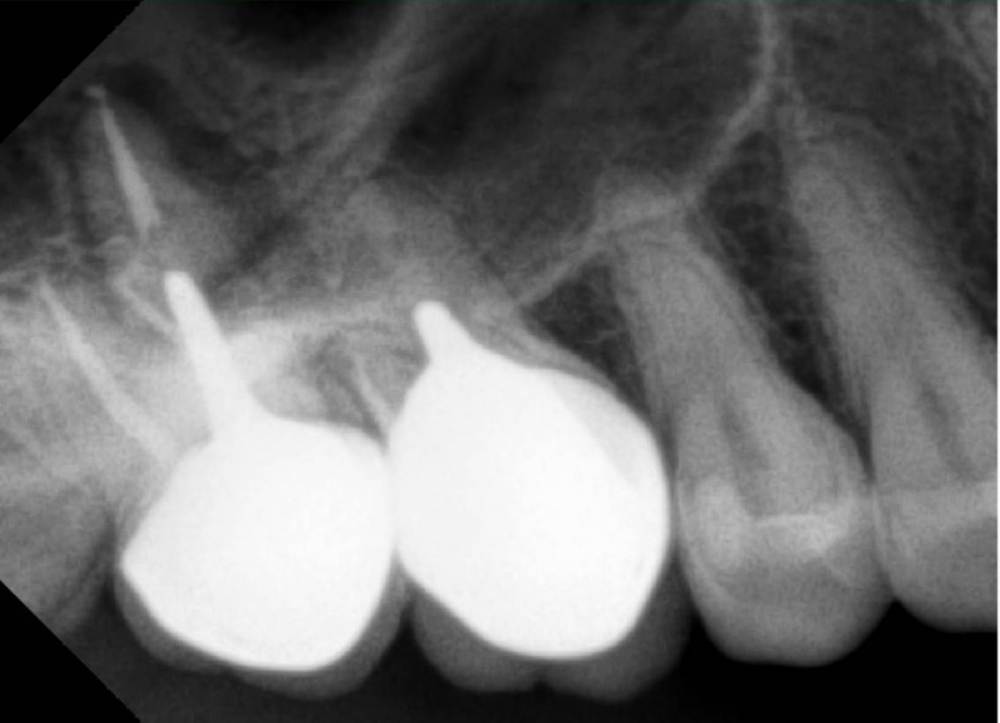

Три года назад на верхние 6 и 7 справа были поставлены метал-керамические коронки. На одном из них случайно попали в пазуху и там осталось немного пломбировочного материала. Все в принципе было спокойно.  В декабре 2020 удаляем все восьмерки, было страшно за те самые коронки, когда удаляли восьмёрку рядом с ними. Обошлось, все тихо.

Рентенг сегодняшний, доктор-ортопед сказал, что 7-ка немного подвижная, на снимке видит воспаление и необходимо удаление.  Извиняюсь за такой длинный текст, стараюсь приложиться максимум информации которая может быть полезна.

Прошу обратить внимание на снимок и помочь в понимании данной ситуации и в дальнейших действиях с этим зубом.